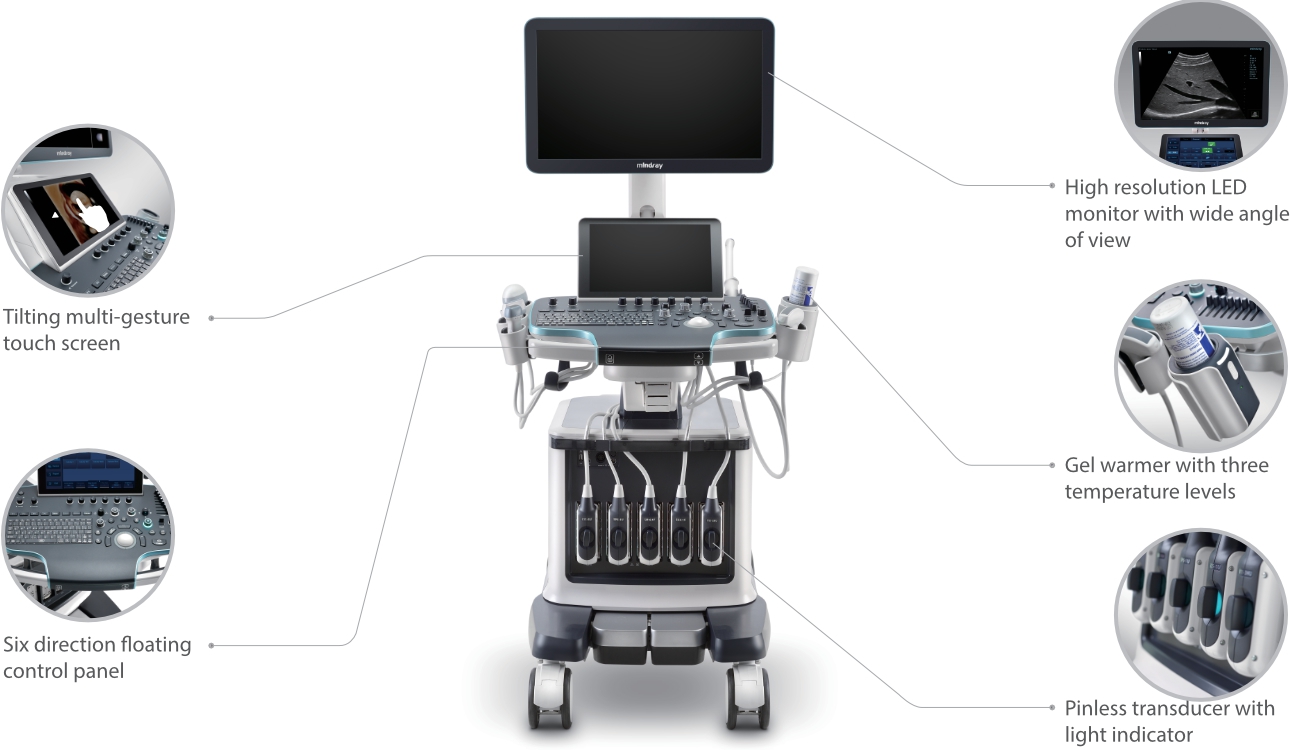

Resona 7

Novas ondas em inova??o de ultra-som

Desde que a empresa foi fundada, a Mindray est├Ī continuamente explorando novas maneiras de melhorar a confian?a no diagn├│stico. Alimentada pela mais revolucion├Īria tecnologia ZONE Sonography?, a nova plataforma Resona 7's ZST+ traz uma qualidade de imagem ultra-som a um n├Łvel superior por aquisi??o de zona e processamento de dados do canal.

Assim como o n├Łvel de qualidade de imagem premium, o Resona 7 tamb├®m melhora as capacidades de investiga??o cl├Łnica com o revolucion├Īrio Fluxo V para avalia??o hemodin?mica vascular e a aquisi??o de plano mais inteligente do conjunto de dados 3D para diagn├│stico CNS fetal. Combinando a opera??o mais intuitiva baseada em gesto de multi-toques e todos os recursos cl├Łnicos essenciais, Resona 7 est├Ī realmente conduzindo novas ondas na inova??o de ultra-som.